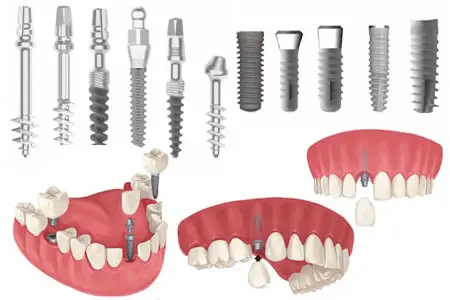

فاصله بین کشیدن دندان و کاشت ایمپلنت برای همه افراد یکسان نیست و به شرایط دهان و فک هر بیمار بستگی دارد. بهطور کلی، کاشت ایمپلنت میتواند در چهار بازه زمانی مختلف انجام شود. در روش ایمپلنت فوری، ایمپلنت در همان روز کشیدن دندان یا حداکثر تا ۷۲ ساعت بعد کاشته میشود که این روش تنها در صورتی انجامپذیر است که عفونت فعال وجود نداشته باشد و استخوان فک از استحکام کافی برخوردار باشد. روش رایجتر، ایمپلنت زودهنگام است که معمولاً ۴ تا ۸ هفته پس از کشیدن دندان انجام میشود؛ در این فاصله، بافت نرم لثه ترمیم شده، التهاب کاهش مییابد و در عین حال تحلیل استخوان هنوز شدید نشده است. در بسیاری از بیماران، این بازه زمانی بهترین تعادل بین سرعت درمان و موفقیت ایمپلنت را ایجاد میکند.

در شرایطی که عفونت شدید، آسیب استخوانی یا التهاب گسترده وجود داشته باشد، دندانپزشک معمولاً ایمپلنت با تأخیر را توصیه میکند که حدود ۳ تا ۶ ماه پس از کشیدن دندان انجام میشود تا استخوان و لثه بهطور کامل ترمیم شوند. در مواردی که نیاز به پیوند استخوان یا سینوس لیفت وجود دارد، فاصله بین کشیدن دندان و کاشت ایمپلنت ممکن است به ۶ ماه یا بیشتر نیز برسد. در نهایت، تعیین زمان دقیق کاشت ایمپلنت تنها پس از معاینه تخصصی و بررسی تصاویر رادیوگرافی مانند CBCT امکانپذیر است و انتخاب زمان مناسب، نقش مهمی در افزایش طول عمر و موفقیت ایمپلنت دندان دارد.

بهترین زمان برای کاشت ایمپلنت دندان به شرایط دهان، استخوان فک و سلامت لثه هر فرد بستگی دارد، اما در بسیاری از موارد، دندانپزشکان بازه ۲ تا ۴ ماه پس از کشیدن دندان را بهعنوان زمان ایدهآل توصیه میکنند. در این فاصله زمانی، بافت لثه و استخوان فک فرصت کافی برای ترمیم اولیه پیدا میکنند، التهاب کاهش مییابد و ناحیه کشیدهشده به ثبات مناسبی برای پذیرش پایه ایمپلنت میرسد. از سوی دیگر، این بازه هنوز آنقدر طولانی نیست که تحلیل قابل توجه استخوان رخ دهد، به همین دلیل شانس موفقیت ایمپلنت بالا باقی میماند.

در بازه ۲ تا ۴ ماهه پس از کشیدن دندان، معمولاً تغییر محسوسی در موقعیت لثه و دندانهای مجاور ایجاد نمیشود و دندانپزشک میتواند بدون نیاز به درمانهای تکمیلی مانند پیوند استخوان یا جراحیهای اضافی، ایمپلنت را با دقت و ایمنی بالا قرار دهد. همین موضوع باعث میشود مدت زمان جراحی کوتاهتر، روند جوش خوردن ایمپلنت با استخوان سریعتر و هزینه نهایی درمان کمتر شود. هرچه کاشت ایمپلنت زودتر و در زمان مناسب انجام شود، مدت نقاهت بیمار کاهش یافته و بازگشت به شرایط طبیعی زندگی و جویدن غذا در زمان کوتاهتری امکانپذیر خواهد بود.

فاصله بین کشیدن دندان و کاشت ایمپلنت نقش تعیینکنندهای در موفقیت درمان، حفظ استخوان فک و کاهش هزینههای آینده دارد. پس از کشیدن دندان، تحلیل استخوان فک میتواند از هفتههای ابتدایی آغاز شود و در صورت تأخیر، منجر به جابهجایی دندانهای مجاور، تغییر فرم لثه و حتی تغییر ظاهر صورت شود. به همین دلیل، انتخاب زمان مناسب برای ایمپلنت اهمیت زیادی دارد. در حالت کلی، ایمپلنت میتواند بهصورت فوری، زودهنگام یا با تأخیر انجام شود، اما در بسیاری از بیماران، بازه ۲ تا ۴ ماه پس از کشیدن دندان بهعنوان زمان ایدهآل توصیه میشود؛ زیرا تعادل مناسبی بین ترمیم بافتها و جلوگیری از تحلیل استخوان ایجاد میکند. با این حال، شرایط هر بیمار متفاوت است و عواملی مانند تراکم استخوان، وجود عفونت، محل دندان و سلامت عمومی فرد در این تصمیم نقش اساسی دارند.